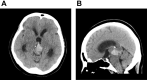

Tumors in the pineal region usually present with acute hydrocephalus. Histologic diagnosis is most important, as it greatly influences treatment, because over 17 tumor types occur in this area. Biopsies of these lesions play an important role in further management. Pineocytomas are benign and rare tumors that typically exhibit a slow progression. However, the appropriate treatment for pineocytoma varies. Surgical excision was considered for good long-term outcomes; however, this may not always be possible. Radiotherapy also appears to be effective in patients with residual pineocytomas. We report a case of pineocytoma with hemorrhagic transformation and complicated hydrocephalus. The patient refused to undergo aggressive tumor excision. Thus, the patient only underwent endoscopic biopsy and external ventricular drain (EVD) implantation, but the outcome was acceptable. In addition, we reviewed the current management strategies for pineocytomas in the literature.